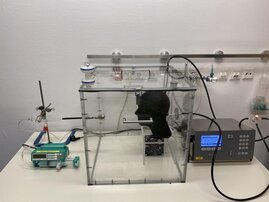

OP-Masken halten Aerosole besser ab als ein starrer Atemschutz ohne EU-Zertifikat – das belegt ein Team aus der Marburger Medizin mit praxisnahen…